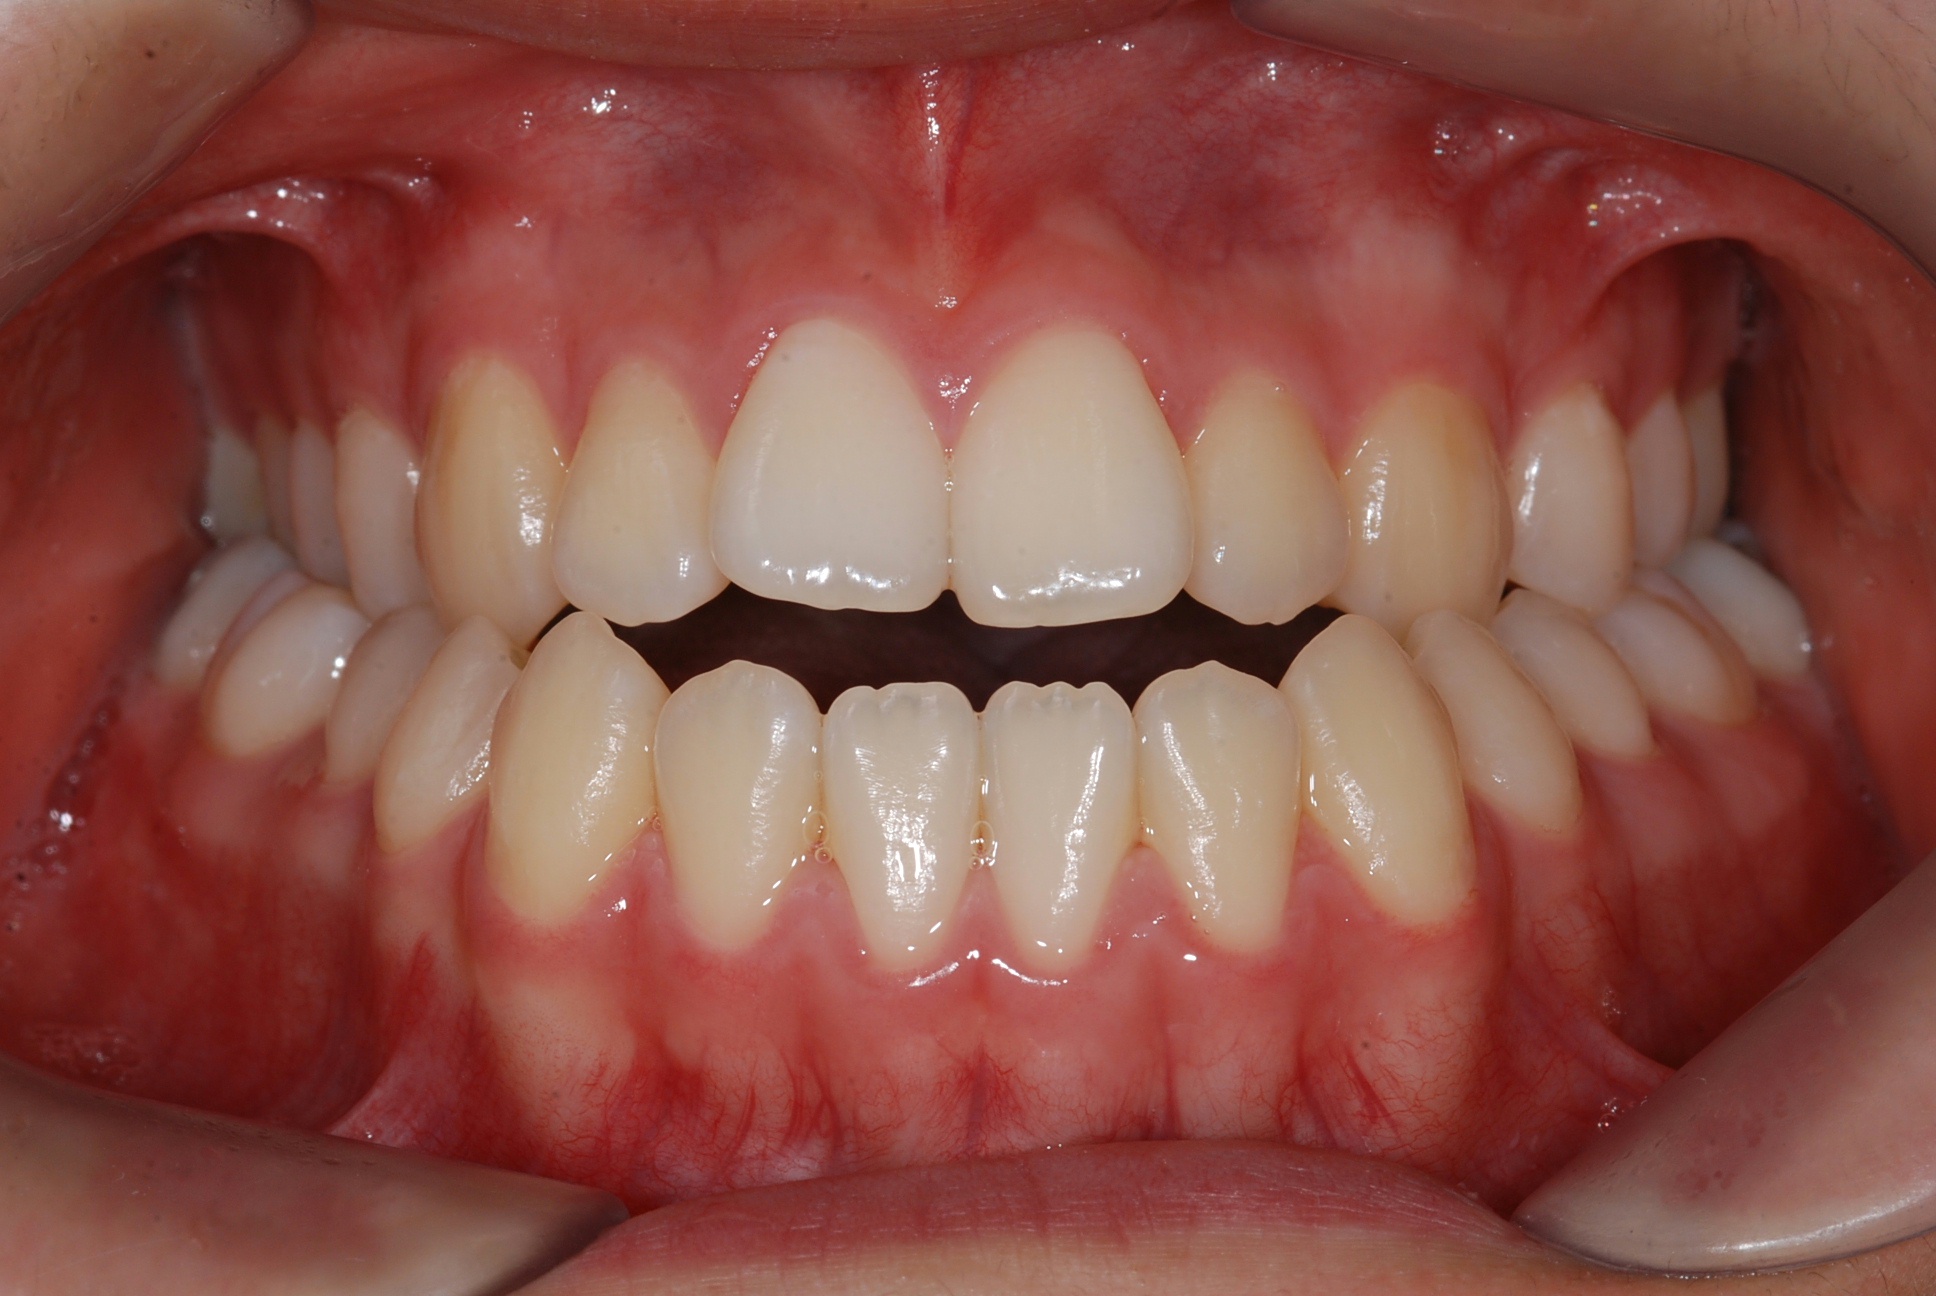

치료 전 사진입니다.